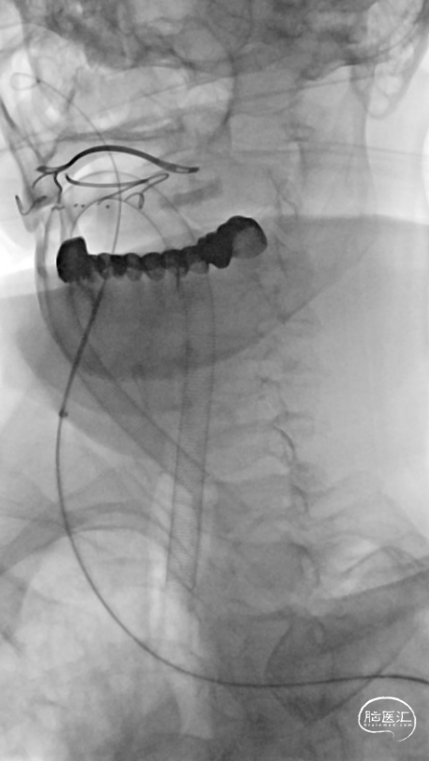

将Synchro(0.014×300cm)微导丝外衬Gateway(2.0×15mm)球囊缓慢通过RMCA M1段狭窄处,球囊定位于RMCA狭窄处缓慢扩张,压力6atm。采用交换技术置入灌注微导管,并将4.0×16mm支架定位于狭窄处释放。

复查造影见支架展开良好,支架内及远端血流通畅,TICI分级3级。术顺,术毕,Proglide缝合术口。